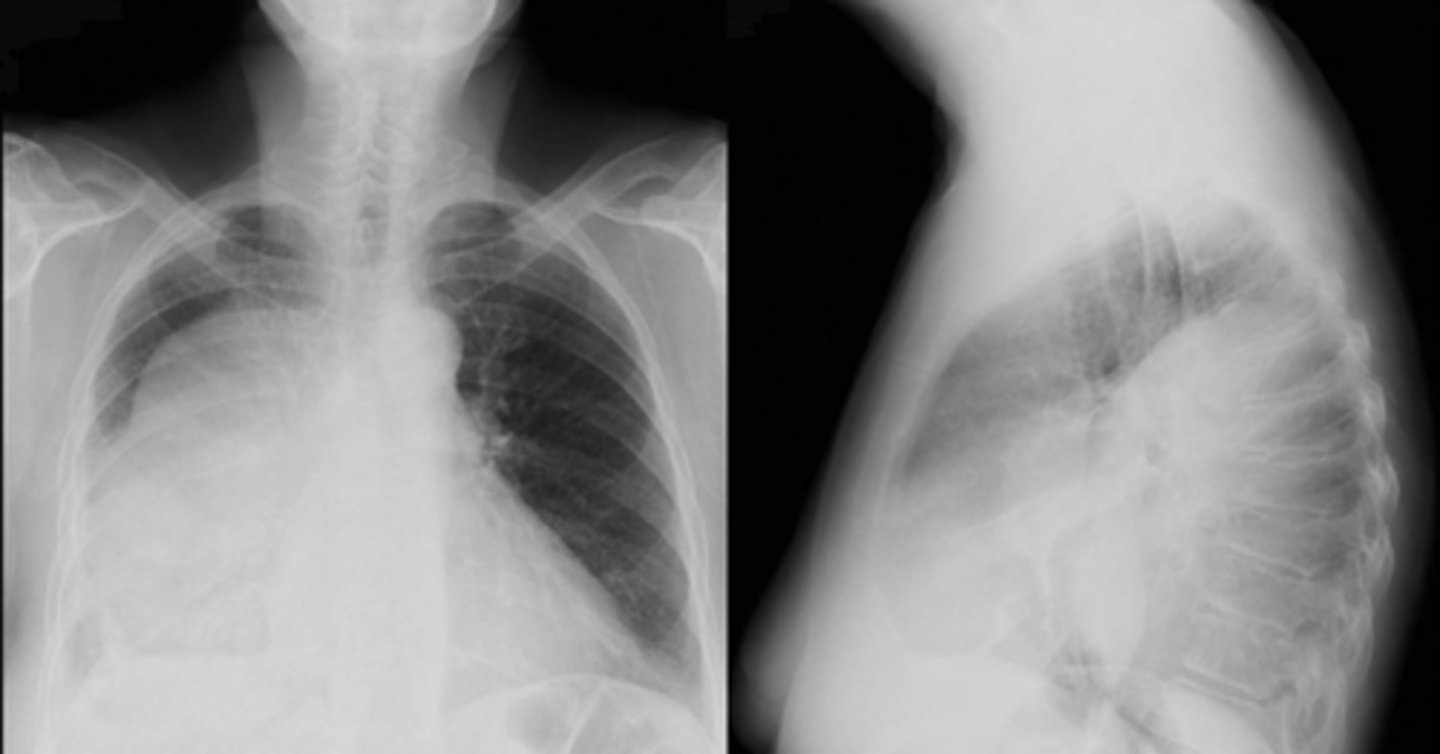

Atelectasis

Atelectasis (RUL)

Linear atelectasis (often seen post-op)

Right sided atelectasis

Atelectasis (right)

Atelectasis LLL